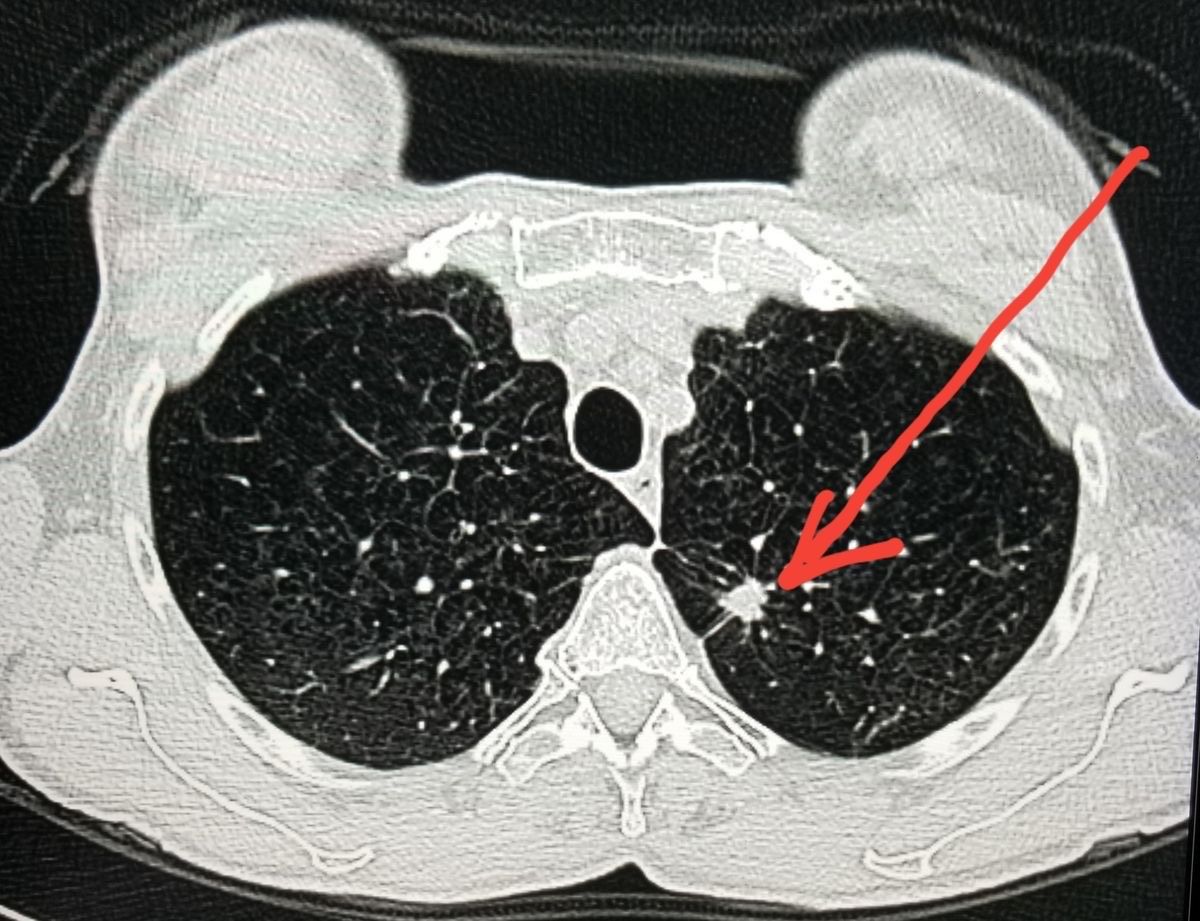

A CT lung scan produces highly detailed images of the lungs and chest, allowing early detection of diseases that can remain hidden for months or even years. This level of clarity helps spot abnormalities that often go unnoticed until they have advanced.

A board-certified radiologist carefully reviews every scan, looking for early signs of disease, including nodules, inflammation, tumors, infections, and lesions.